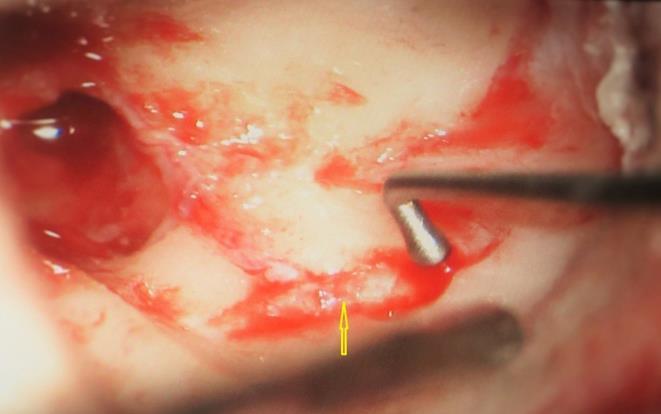

A 13 year old girl presented in ENT outpatient department with complains of recurrent right ear purulent discharge from pre and post auricular area for last 5 years. She had a history of incision and drainage in right post auricular area six months prior for similar complain. On local examination, there was right Grade II8microtia with atretic External Auditory Canal (EAC) and pre-auricular skin tag (Figure 1). A small fistulous opening was also seen in right cavum conchae region. Left ear examination was normal with intact tympanic membrane. Tuning fork tests using 256 and 512 Hz tuning forks showed moderate to severe conductive hearing loss in right ear with Rinne’s test positive in left ear. HRCT scan of temporal bones showed membranous atresia of right EAC with grade II microtia. Soft tissue density was seen filling the EAC and the entire middle ear cavity (Figure 2A). A CT based fistulogram done four months before our consultation identified multiple fistulous tracts situated in post auricular region and anterior to stylomastoid foramen in inframastoid region. These fistulous tracts were communicating through middle ear cavity (Figure 2B). There was associated erosion of posteroinferior and anteroinferior wall of EAC. Ossicles were dysplastic or eroded. Inner ear structures were normal. Patient underwent right radical mastoidectomy with wide conchal meatoplasty under general anaesthesia. Intraoperatively, there was right EAC membranous atresia with fistulous opening in cavum conchae. Cholesteatoma sac was seen filling the mastoid antrum area extending into middle ear cavity and EAC with erosion of posterior canal wall. Except remnant of malleus head which was fixed to epitympanic wall, no other ossicle was found. Oval window area showed bony depression without any overlying stapes footplate (Figure 3). Lateral semicircular canal bulge, facial nerve canal and chorda tympani were found at their usual locations (Figure 4). Obliteration of mastoid cavity posterior to vertical segment of bony facial canal was done using pedicled temporalis muscle flap to reduce the size of postoperative cavity. Middle ear cavity was covered with temporalis fascia graft.

Figure 3.Arrow pointing towards oval window area

Arrow pointing towards oval window area